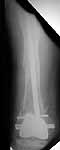

Well, finally i still performed antegrade nailing. After the distractor was applied, reduction of the recent fracture was obtained "automagically".

But the previous fracture resulted with some posterior displacment of the distal part, so antegrade nail would pass anteriorly, and retrograde nail, even a short one, would have penetrated anterior cortex proximally to the fracture. So perQ osteotomy was necessary to add some mobility at the level, and after that the nail was easily inserted to the distal fragment. The nail is solid, 13 mm, locking screws 6 mm. Locked statically.

The radiographs look excellent and a good outcome would be anticipated. The idea to osteotomize the femur shaft to compensate for the prior shaft malunion was clever and should work fine. I can't actually see the osteotomy on either radiograph. Is it more proximal than we see in these radiographsor so well aligned as to be not visible? Have you tried retrograde femoral nailing? Most people find it technically easier although not necessarily better than antegrade.